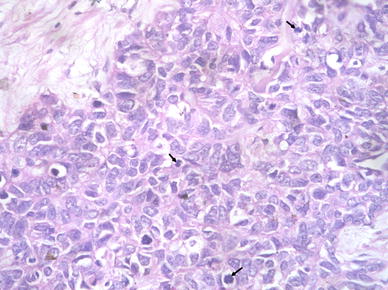

On surgical resection, the tumor was vascular, encasing the facial nerve and infiltrating the subcutaneous tissue and adjoining fat planes. On gross examination, the tumor measured 5 × 4 × 2 cm and replaced the entire parotid except for a thin wedge of grossly uninvolved tissue at one side. The cut surface of the tumor was variegated with solid, cystic, hemorrhagic and necrotic areas. On microscopic examination the tumor was primarily composed of sheets and nests of cells with intermediate to large-sized hyperchromatic nuclei, prominent nucleoli, scant eosinophilic cytoplasm and frequent mitosis (>20/10 hpf) (Fig. 2). The tumor nests were devoid of surrounding myoepithelial cells. Areas of necrosis (~10% of tumor area) and desmoplasia were seen. No intratumoral calcification was present. A discrete focus of conventional adenoid cystic carcinoma (grade II) occupying <10% area of the studied sections was identified. The tumor cells in this focus were arranged entirely in cribriform pattern showing small basaloid cells with interspersed pseudocystic spaces containing fuschinophilic acellular hyaline material and infrequent mitosis (~1/10 hpf; Fig. 3). Extensive perineural and lymphovascular invasion by tumor cells was seen. The tumor was diffusely infiltrating the adjoining salivary gland, fibrofatty tissue and skeletal muscle. A single lymph node was identified in the attached fat, metastatic deposits in which showed presence of high grade areas along with few foci of conventional ACC. A retrospective review of the fine needle aspirate smears revealed few small aggregates of isomorphic basaloid cells.

Fig. 2

High grade ACC component showing pleomorphic undifferentiated cells with frequent mitoses (arrows)